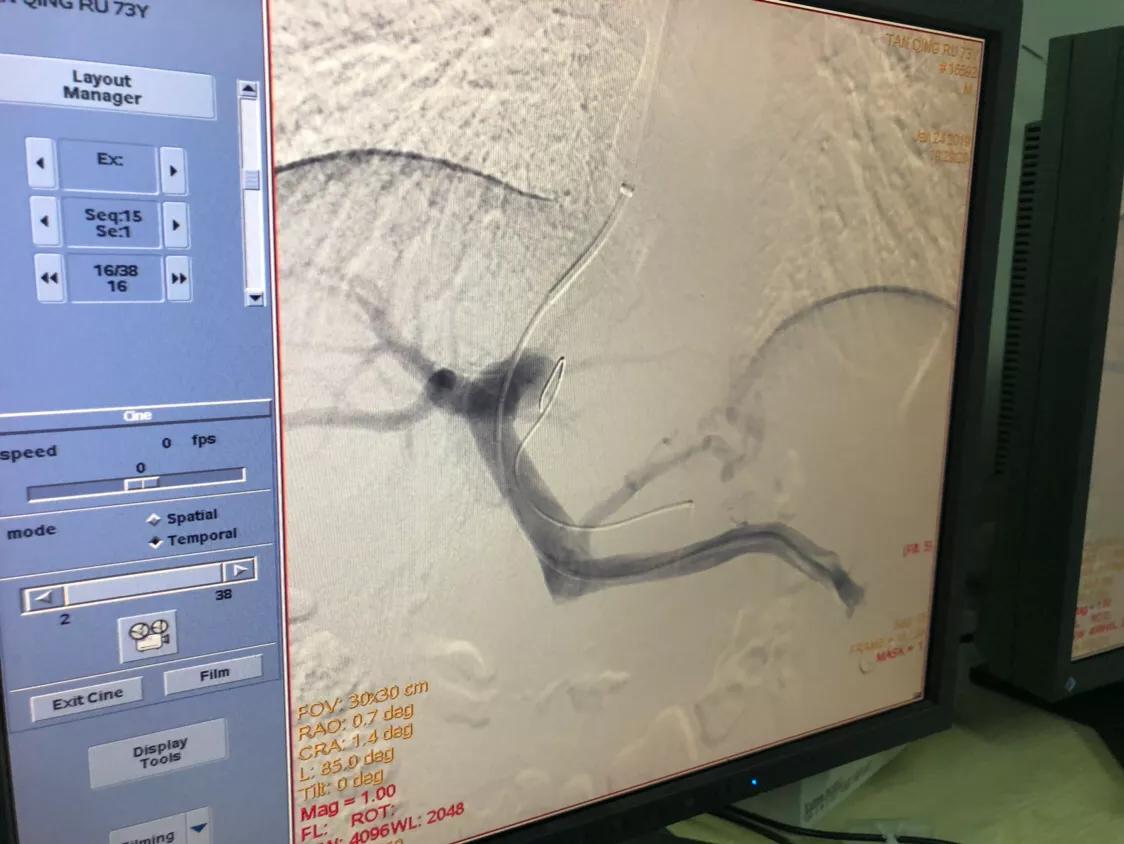

全主任与刘震坤医生虽多次开展TIPS手术,技术成熟精准,可是血吸虫肝硬化患者,还是第一例,因此介入团队的专家对李大伯的手术非常慎重,在完善术前准备后,据病情特意为他制定了详实的手术治疗方案及应对措施,并于周四顺利为其进行了TIPS介入手术。

现在我们来听听刘医生介绍这位患者的TIPS手术(经颈静脉肝内门腔静脉内支架分流术)。

Tips是治疗肝硬化门静脉高压胃食管静脉曲张破裂出血、门脉高压腹水的介入新技术,手术全程在血管腔内操作,通过血管穿刺、球囊扩张和支架植入技术,在肝内通过穿刺在肝静脉和门静脉之间创建一个人工血管通道达到引流门脉血流,降低门脉压力的目的。Tips手术对病人创伤小(仅颈静脉一约3mm穿刺伤口),恢复快,术中还可有效祛除曲张静脉同时降低门静脉压力,是治疗肝硬化门脉高压最有效的微创手术方法。